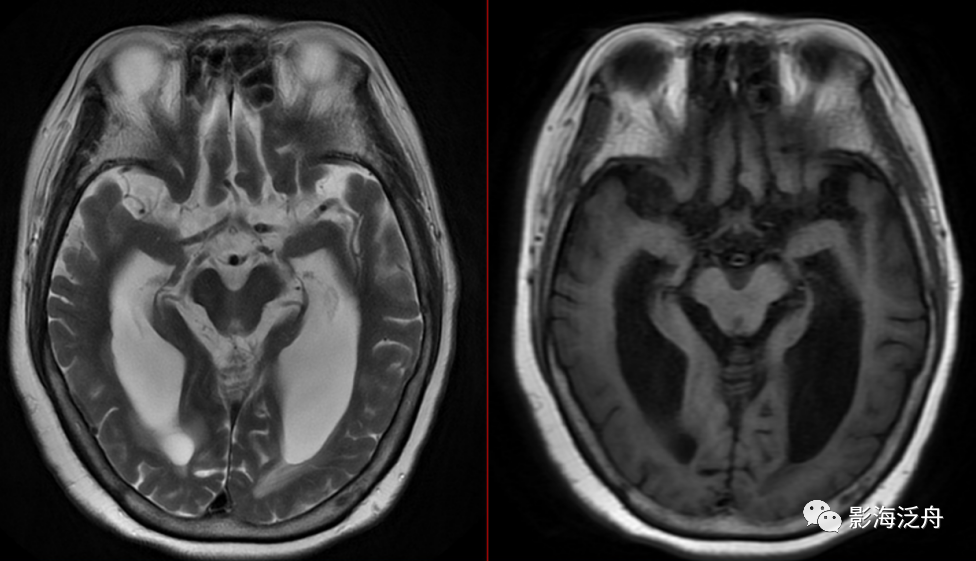

患者,女,68岁,4天前无明显诱因出现头痛头晕伴走路不稳,症状呈持续性,能耐受,休息后无缓解,伴反应迟钝,无恶心呕吐,无肢体活动障碍,无口齿不清等不适。既往小便失禁1年余,否认高血压、糖尿病、肿瘤史。否认食物、药物过敏史。神经系统查体巴氏征可疑阳性,余无殊。为进一步明确诊断,行颅脑MR平扫+增强检查,影像资料如下↓↓↓

结合患者的临床表现及影像资料,您诊断什么?脑萎缩伴脑积水?这个只能算是单纯的影像学诊断,无法解释患者的临床表现,对于临床治疗更没有什么参考价值。那应该考虑什么?住院后患者经过脑脊液放液治疗,上述症状明显改善,诊断为正常压力脑积水。

尽管脑脊液压力正常,但NPH患者的脑积水程度进行性加重,因此常可见到间质性脑水肿表现(红箭头),这种间质性脑水肿在LAIR序列上表现为沿侧脑室均匀分布的带状高信号,与脑白质疏松有较大区别。